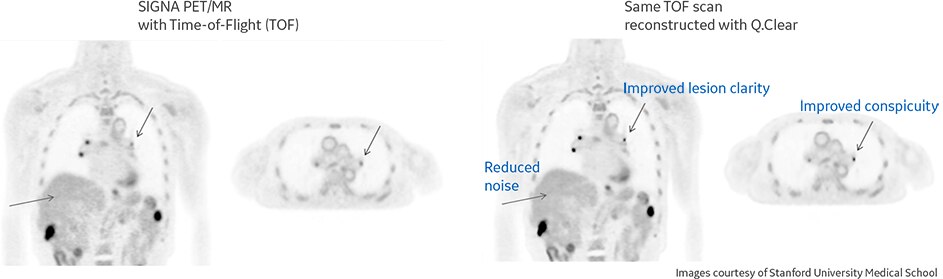

Increased PET sensitivity with TOF and QStatic